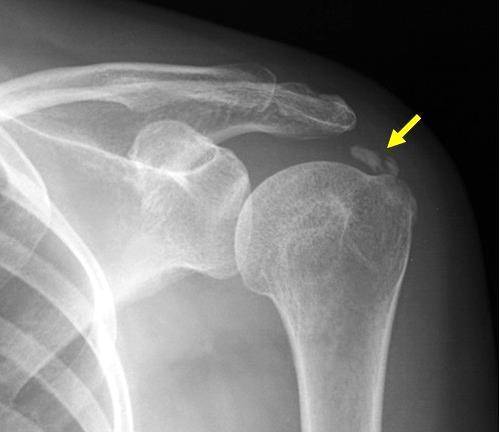

오히려, 칼슘보충제 복용으로 높아진 칼슘 수치는 심혈관을 석회화시켜 심각한 문제를 일으킬 뿐만 아니라, 팔이나 다리 혹은 어깨의 인대나 힘줄에 석회를 침착시켜 '석회성 건염'(calcific tendinitis)을 유발하기도 한다 (아래 사진) [3].